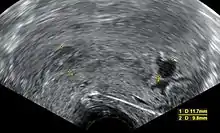

Ultrasound criteria

A review article in The New England Journal of Medicine based on a consensus meeting of the Society of Radiologists in Ultrasound in America (SRU) has suggested that miscarriage should be diagnosed only if any of the following criteria are met upon ultrasonography visualization:[93]

| Crown-rump length of at least 7 mm and no heartbeat. | Crown–rump length of less than 7 mm and no heartbeat. | [93][94] |

| Mean gestational sac diameter of at least 25 mm and no embryo. | Mean gestational sac diameter of 16–24 mm and no embryo. | [93][94] |

| Absence of embryo with heartbeat at least 2 weeks after an ultrasound scan that showed a gestational sac without a yolk sac. | Absence of embryo with heartbeat 7–13 days after an ultrasound scan that showed a gestational sac without a yolk sac. | [93][94] |

| Absence of embryo with heartbeat at least 11 days after an ultrasound scan that showed a gestational sac with a yolk sac. | Absence of embryo with heartbeat 7–10 days after a scan that showed a gestational sac with a yolk sac. | [93][94] |

| Absence of embryo at least 6 weeks after last menstrual period. | [93][94] | |

| Amniotic sac seen adjacent to yolk sac, and with no visible embryo. | [93][94] | |

| Yolk sac of more than 7 mm. | [93][94] | |

| Small gestational sac compared to embryo size (less than 5 mm difference between mean sac diameter and crown–rump length). | [93][94] |